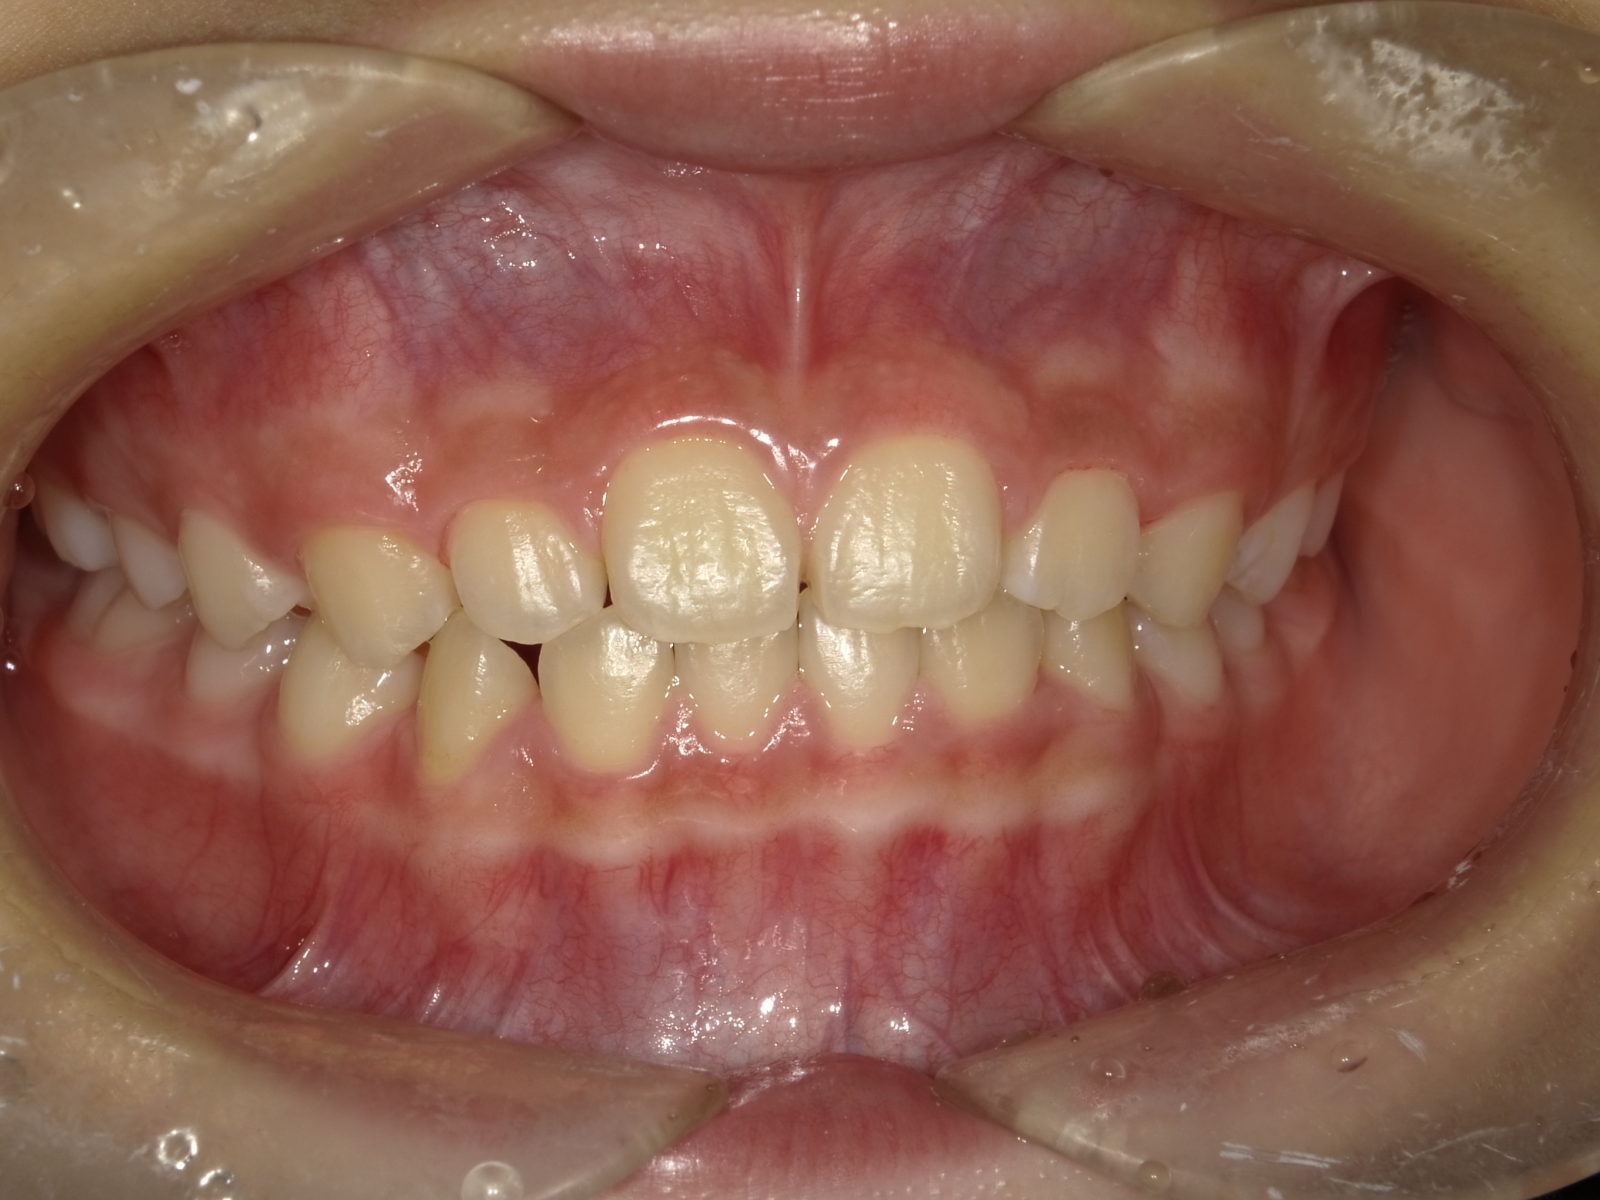

顎顔面矯正の説明をする前に、「なぜ子供の歯並びが悪くなるの?」に関してお答えします。

簡単にお伝えすると、歯が生える土台の「顎」が昔と比べて小さくなっているためです。

狭い顎に無理矢理歯が並ぼうとするので、ガチャガチャになるのです。

つまり、歯が適切に並ぶように「顎のスペースを広げる」ことが重要になります。

顎顔面矯正も「顎のスペースを広げるアプローチ」を行う矯正手法ですが、床矯正のデメリットをすべて改善しています。その他、次のようなメリットも期待できる矯正治療です。

顎顔面矯正は一般的な矯正と異なり「顎を拡大」するのですが、特に「上の顎」を拡大することが大きな特徴です。これを行うことで、先ほどのメリットが副次的効果として生まれます。

顎顔面矯正は、「急速拡大装置」を利用し、正中口蓋縫合と呼ばれる部分を広げ、顎骨の成長を促していきます。下の画像のように「ねじ」を回すことで装置を徐々に広げていきます。